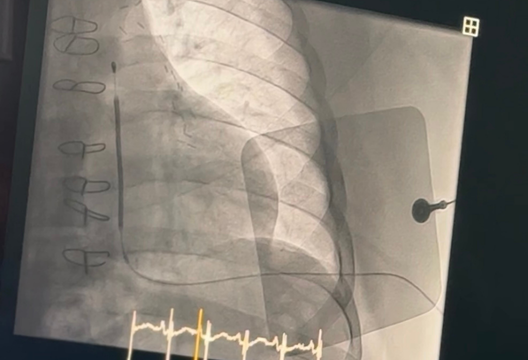

Имплантацияланатын кардиовертер дефибрилляторлары (ИКД) ауыр тахикардия және жүрек ырғығының бұзылуы бар көптеген пациенттерді емдеуде таптырмас көмекші болды. Бұл құрылғылар жүректің тез жиырылуы немесе кенеттен тоқтауы жағдайында құтқару терапиясы болып табылады. Дәстүр бойынша, ИКД мойын сүйектерінің жанындағы сол жақ иық аймағына имплантацияланады. Рентгенография пайдаланып жүрекке тамыр арқылы, содан кейін қақпақша арқылы арнайы сымдар енгізіліп, жүректің ішкі қабырғасына бекітіледі.

Сондай-ақ, шеберлік сабақтың аясында Италиядан келген сарапшы қауіпсіз баламаны қамтамасыз ететін EMBLEM™ S-ICD System тері астындағы ИКД имплантациялау технологиясын ұсынды. Бұл құрылғы жүрекке электродты енгізуді қажет етпейді, бірақ терінің астына төс сүйегінің үстіне қойылады. Импульстік генератордың өзі кеуде қуысының сол жағына, қабырғалардың жанына орналастырылады. Осылайша, EMBLEM жүйесі жүрек пен қан тамырларына әсер етпейді. Бұл құрылғы әртүрлі жастағы пациенттерге қолайлы, ауыр асқынулардың қаупін азайтады және қажет болған жағдайда шығаруды жеңілдетеді және жылдамырақ етеді.